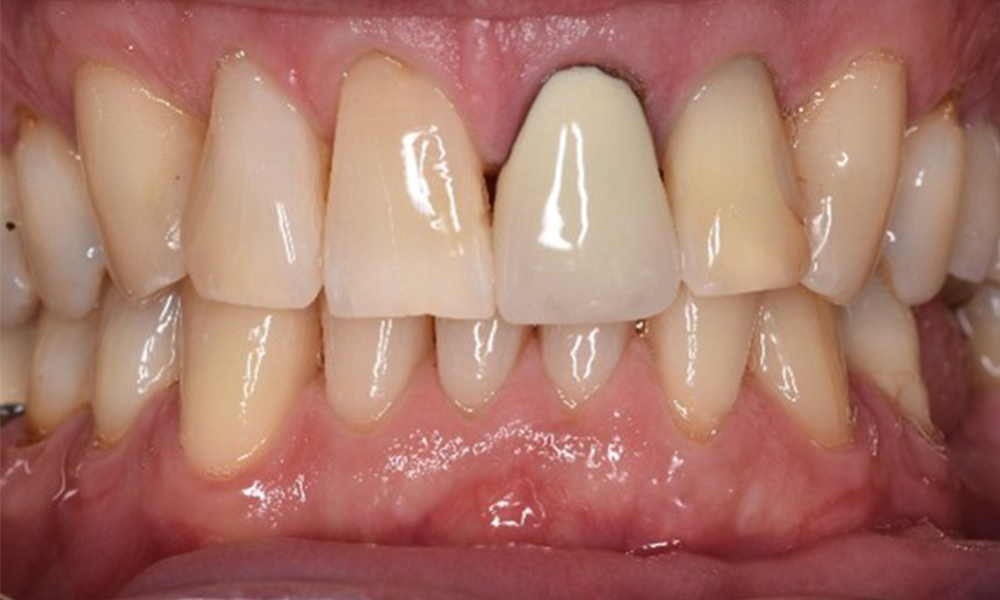

Der Patient hat einige zahnärztliche Restaurationen und zwei Implantate (2. und 4. Quadrant). Anhand der aktuellen Befunde lässt sich eine Gingivitis bei stabilem parodontalen Zustand am reduzierten Parodont (Stadium III, Grad A) feststellen.

Versorgungen: zahnärztliche Restaurationen (NEM keramisch verblendet), zwei Implantate (2., 4. Quadrant)

Trotz der stabilen Verhältnisse ist auch bei diesem Patienten die Motivation/Instruktion wichtig. Besonderes Augenmerk gilt der richtigen Implantatpflege. Gerade hier kann eine gute häusliche Pflege einen wichtigen Anteil an der langfristigen Stabilisierung der Mund- und Implantatgesundheit haben.